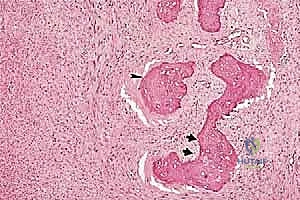

تتميز هذه الأورام بقدرتها على اختراق الأنسجة المجاورة وتكوين ما يُعرف بـ "المنطقة التفاعلية" (Reactive Zone) أو الكبسولة الكاذبة، والتي تحتوي غالباً على خلايا سرطانية مجهرية. هذا المفهوم البيولوجي هو ما يوجه الدكتور محمد هطيف في تحديد مدى الاستئصال الجراحي.

تحديد مراحل الورم (Staging): نظام Enneking

تحديد مرحلة الورم هو الخطوة الأهم قبل أي تدخل جراحي. يعتمد الدكتور هطيف على نظام (Enneking) لتحديد مراحل أورام العظام، والذي يعتمد على ثلاثة عوامل:

1. درجة الورم (Grade - G): بناءً على الفحص النسيجي (G1 منخفض الدرجة، G2 عالي الدرجة).

2. الموقع (Site - T): هل الورم داخل الحيز العظمي (Intracompartmental - T1) أم اخترق القشرة وخرج للحيز الخارجي (Extracompartmental - T2)؟

3. الانتشار (Metastasis - M): هل انتقل الورم لأعضاء أخرى (M0 لا يوجد، M1 يوجد انتشار)؟

بناءً على هذا التقييم الدقيق، يتم وضع خطة جراحية متكاملة لضمان استئصال الورم بالكامل دون ترك أي خلايا سرطانية.